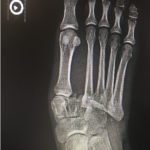

The frontal view of the right foot showed divergent dislocation of the second through fifth metatarsal bones (red outlines) consistent with Lisfranc injury. Though the Lisfranc ligament is not visualized by radiograph, the yellow markings represent the location of the Lisfranc ligament between the medial cuneiform (blue dot) and the base of the second metatarsal bone. The first metatarsal and the medial cuneiform remain congruent. The lateral view shows dorsal dislocation of the midfoot (pink circle) consistent with instability. There is associated extensive midfoot soft tissue swelling.